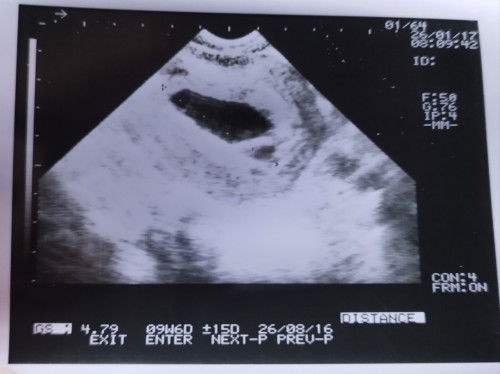

Bun minta arahannya. aku USG 11 weeks, sdngkan di hpht sdh 14 weeks. di vonis bo. flek sdh seminggu, trus keluar darah segar sedikit (satu kali), perut kram trus tiap 15 menit. aku harus gmn bun? Sdh usg transvaginal hasilnya ini 👇🏻#mohonbantujawabbunda #Sharingdong_Bund #bantujawab #firstmom #sharing #askmommies #Needadvice